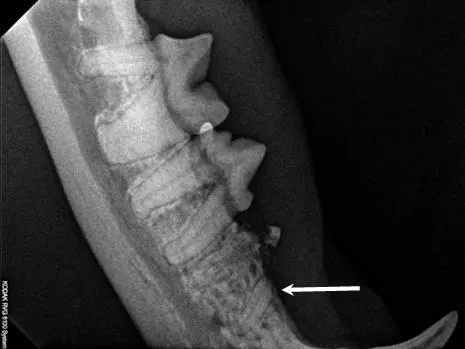

Step 1

Intraoral radiograph of #407 shows a clearly defined intact mesial root (arrow) and ill-defined distal root with type 2 resorption. The clinical lesion of gingivitis is noted over the retained mesial root.